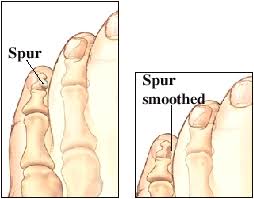

Hallux Rigidus Stiff Big Toe OrthoInfo AAOS

Treatment of Arthritis in the Bunion Joint also known as Hallux

Bone Spurs Clinton Twp Macomb MI See a Top Podiatrist Today

Storm Anesthesia The Stiff Big Toe Joint Hallux Rigidus

Spurs Treatment Foot Doctor Southlake Keller Flower Mound

Hallux Limitus Big Toe Joint Arthritis St. Catharines Ontario